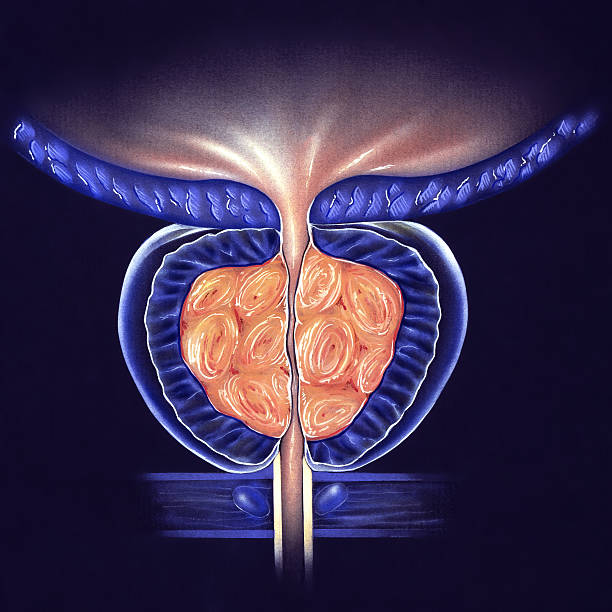

전립선은 남성 생식 기관으로 정자로 들어가는 체액을 생성하는 역할을 합니다. 이러한 전립선액은 남성 생식력에 필수적으로 샘은 방광의 목에 있는 요도를 둘러싸고 있습니다. 방광경부는 요도가 방광과 만나는 곳으로 방광과 요도는 하부 요로의 일부입니다. 전립선은 조직의 바깥층으로 둘러싸인 두 개 이상의 엽 또는 섹션을 가지고 있으며 방광 아래 직장 앞에 위치하며 요도는 방광에서 몸 밖으로 소변을 운반하는 관으로 요도는 음경을 통해 정액을 운반하는데 그 부위에 염증이 생기는 것을 전립선염이라고 합니다. 이러한 증상은 전립선 및 때로는 전립선 주변 부위의 염증과 관련된 지속적인 통증이 생기는 것을 의미하며 이번 시간에는 전립선염으로 생길 수 있는 여러 증상에 대해 정리해보겠습니다.